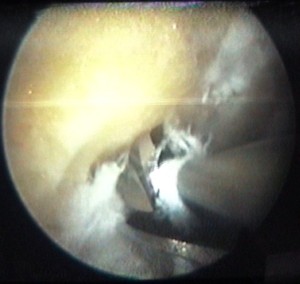

cette vis sert à attacher le ligament |

et elle est maintenant vissée à fond |